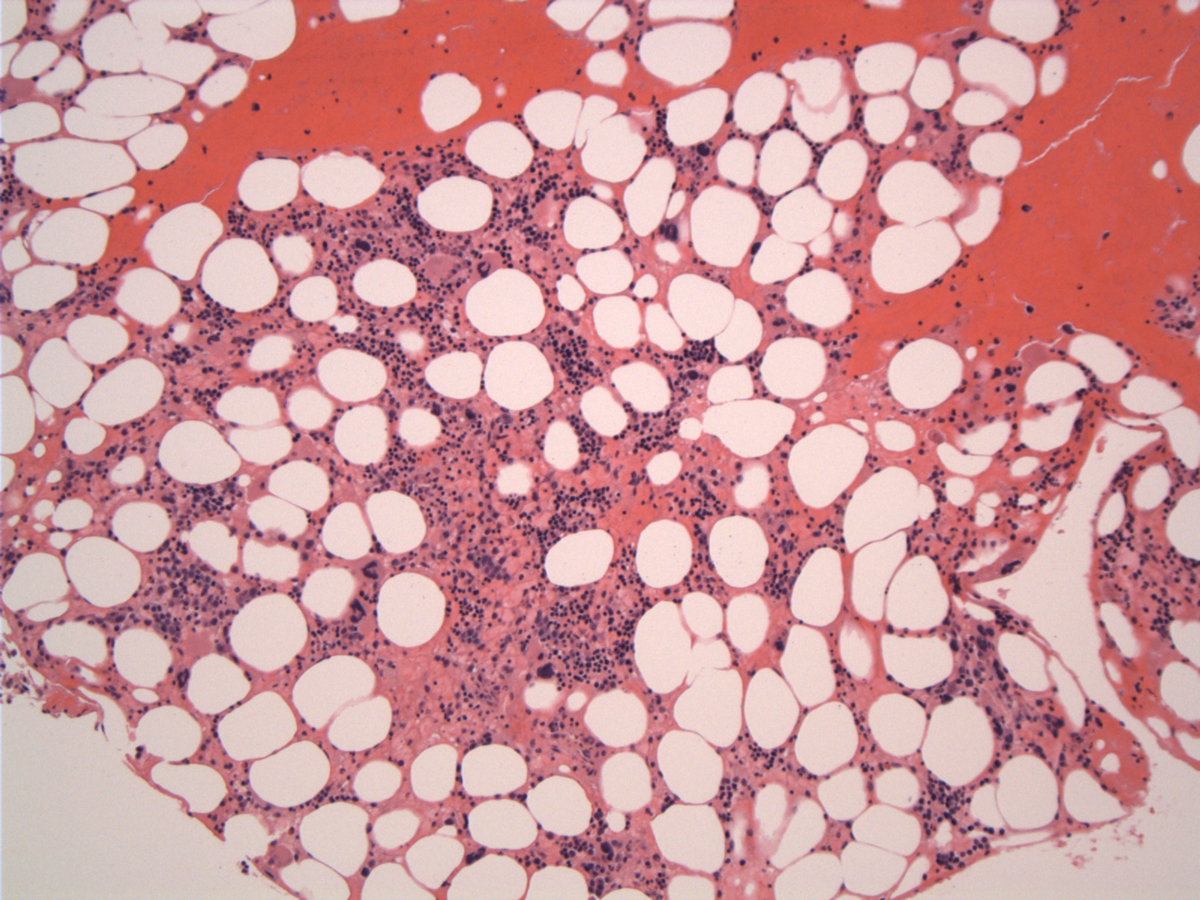

The formalin-fixed, paraffin-embedded biopsy showed hypocellular marrow with markedly decreased granulocytic and erythroid precursors, dyspoietic megakaryocytes, extensive stromal injury and rare interstitial atypical cells, medium to large size, with ovoid nuclei variably condensed chromatin, occasional prominent large eosinophilic central nucleoli and abundant cytoplasm. Rare Reed-Sternberg–like cell were seen but no lymphoid aggregate or fibrosis was identified. In the touch imprints the atypical cells have large or medium-sized hyperchromatic nuclei and large central nucleoli, abundant basophilic cytoplasm with eosinophilic granules. Peripheral blood shows pancytopenia with severe neutropenia, rare Döhle bodies and no circulating tumor cells.

| Bone marrow at presentation-day 1 | ![]() |

| Bone marrow day 9 | ![]() |

| Hypocellular marrow space with stromal injury | ![]() |